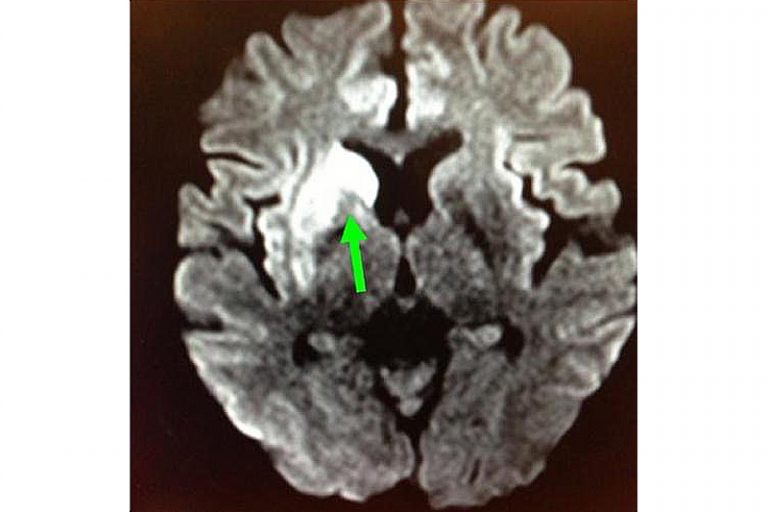

圖:右邊大腦缺血水腫,導致左邊手腳無力和神智半昏迷。

羅先生被送往私家醫院的第一步是進行緊急磁力共振造影,報告顯示羅先生右邊頸和腦部血管大動脈全部都被血栓堵塞着,右邊大腦缺血水腫,導致左邊手腳冇力和神智半昏迷。經過腦血管外科醫生的診斷和急救,在全身麻醉下,醫生使用尤如髪絲微細的導管,經過病人右邊大腿的腹股溝的大動脈而入,導管再經過腹部和胸腔的大動脈一直向上,遊走到病人右邊的頸和腦部血管大動脈,進行機械式血栓吸取內血管治療急救。